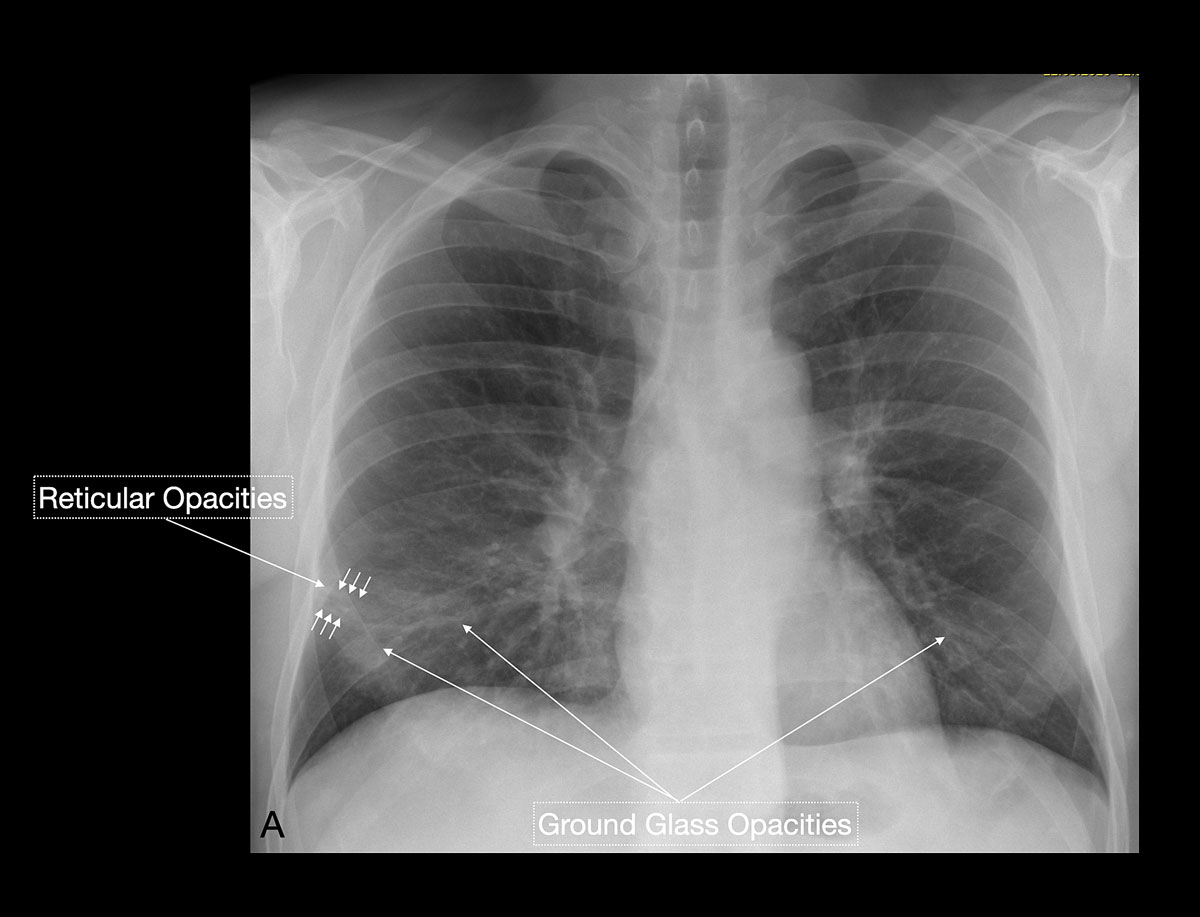

Studies [4, 13, 14] have shown that in early stages, COVID-19 and atypical, interstitial pneumonia share the same primary findings. Typically our patients presented with bilateral reticular (64%) and patchy either ground glass (64%) or consolidative air space opacities (45%), with a peripheral and basal distribution (detailed definitions of these features are illustrated in figs 1 and 2 ). Since ground glass opacities may be very subtle in appearance, their detection on a chest x-ray is sometimes uncertain. Pleural effusions are rare and were seen in only 13% of our COVID-19 patients. In later stages, features of organising pneumonia with accentuated bilateral patchy consolidations were observed (fig. 3).

Figure 2 A 71-year-old male patient with cough, intermittent fever and progressive dyspnoea. Early findings were predominantly peripheral ground glass opacities and reticular opacities. No consolidations or pleural effusions are seen. Subsequent nasopharyngeal RT-PCR test was positive for COVID-19.

Figure 4 A 31-year-old female patient working as a waitress presented with episodes of high fever and progressive shortness of breath. Chest x-ray, performed at the same time as nasopharyngeal RT-PCR testing, showed very subtle evidence of faint ground glass opacities and with a superimposed reticular pattern, which raised the high suspicion of an early stage COVID-19 infection. No consolidation or pleural effusions were evident. RT-PCR test results available after 48 hours confirmed COVID-19.